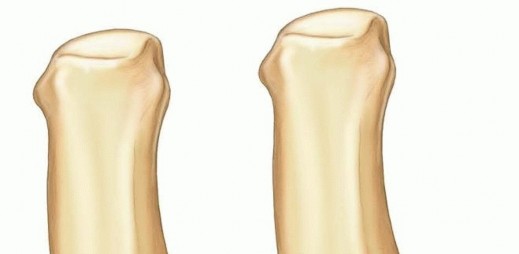

30 MIN READ Primary Repair and Nerve Grafting following Complete Nerve Transection in the Hand, Wrist, and Forearm يناير 2023 Read More